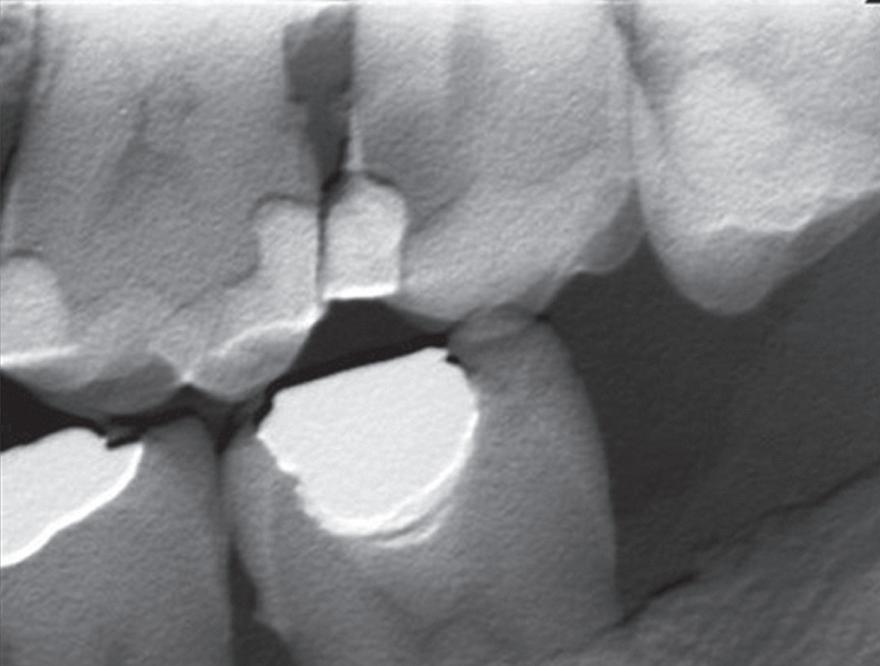

Figure 1: Radiographic Image of implants do not demonstrate bone loss due to the bisecting angle of the radiograph taken.

Figure 2: Radiographic image in a paralleling technique of implants dem onstrate moderate peri-implantitis with bone loss that will necessitate treatment.